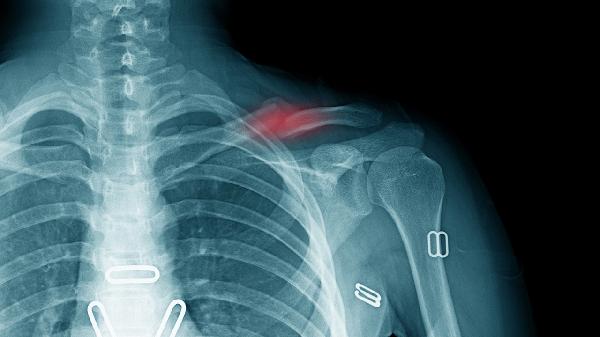

剧烈运动或搬运重物可能导致胸大肌或肋间肌拉伤,表现为局部压痛和活动受限。可通过热敷缓解疼痛,48小时内冷敷减轻肿胀,避免提重物。若疼痛持续超过1周,需排除肋骨骨折可能。

肺部感染或结核累及胸膜时,深呼吸会诱发尖锐胸痛,可能伴有咳嗽发热。需行胸部CT检查,结核性胸膜炎需规范服用异烟肼片、利福平胶囊等抗结核药物,细菌性胸膜炎可使用左氧氟沙星片治疗。